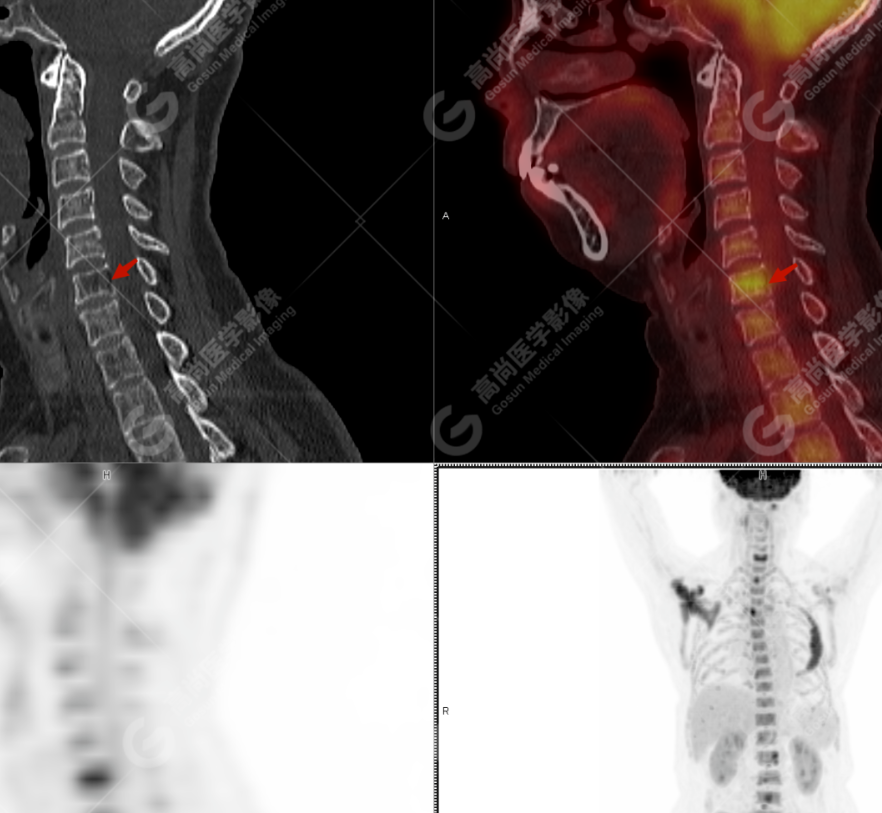

患者,女性,64 岁,因腰痛伴双下肢放射痛 3 月就诊,外院 CT 提示:左侧第四肋骨、右侧肩胛骨及颈 1、6 椎体骨质破坏,考虑转移;于本中心 PET-CT 协诊。既往史:剖宫产;否认外伤史,否认过敏史,否认家族肿瘤史。

颅骨、寰椎前弓左侧份、第 6 颈椎、双侧肩胛骨(右侧为著)、左侧第 4 肋骨、第 1 胸椎、第 4 胸椎、第 2 腰椎及附件、第 4 腰椎及附件、骶骨、右侧髂骨、左侧坐骨结节、左侧股骨颈、双侧股骨小转子等均不同程度骨质吸收、破坏,其中右侧肩胛骨、左侧第 4 肋骨及骶骨右侧份软组织肿块影形成,上述病变均考虑恶性肿瘤(血液系统来源,多发骨髓瘤可能性大),建议右侧髂骨翼穿刺活检明确。

(4)PET-CT 影像表现:在溶骨性破坏区出现相重叠的 18F- FDG 高代谢区;通常呈弥漫性高代谢区。